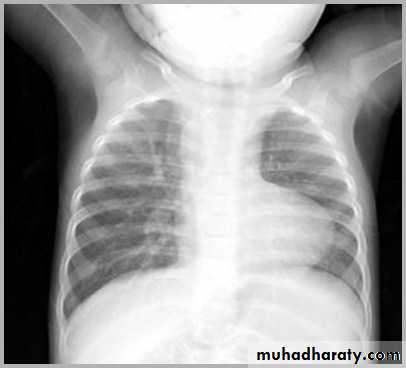

23.normal neonatal chest XR ( normal thymus gland )

24. normal chest XR of the infant( normal thymus gland)